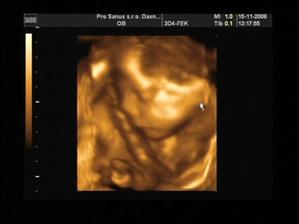

Naše vysnívané bábätko-Davidko

Naše zlatíčko prišlo na svet 7.marca 2007 o 22:25 s váhou 3350g a 51cm 🙂